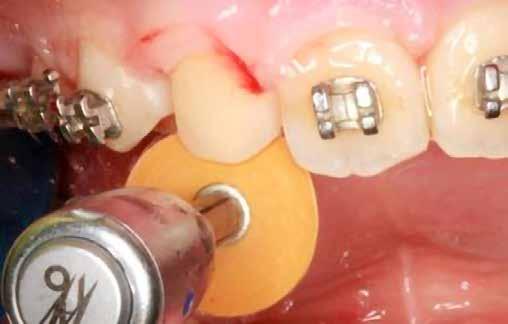

Kisőrlő becsiszolása

Ha a szemfog helyére mezializált kisőrlő intrúziójára nincs is szükség, a palatinális csücsök akkor is akadályozhatja a harapást és a szemfogvezetést [44]. Ezekben az esetekben elcsiszoljuk a palatinális csücsköt (8. a-b ábra) piros gyémántcsiszolóval (finom, 27-76 µm, éli formázóval – Rodentica speciális tűhegy 806314466514031, Komet 8833 vagy GD – lándzsa Rodentica 806314257514020, Komet 0640) gyorsítóban (max 160 000 fordulat/perc) vízhűtés mellett, min. 50 ml/perc [39]. Extra finom sárga gyémántcsiszolóval polírozunk, 10-36 µm szemcsézettséggel (sárga éli csiszoló Rodentica speciális tűhegyű 806314466504031, GD – sárga lándzsa alakú Rodentica 806314257504020) és narancs Sof-Lex korongokkal (3M finom, narancssárga-alumínium-oxid kristály 3-40 µm nagysággal, extra finom, narancssárga-sárga, 1-7 µm alumínium-oxid kristályokkal) könyökdarabban (25 000 fordulat/perc) legalább 50 ml/ min. hűtéssel. Az elcsiszolást több lépésben végezzük, és ezt helyi fluoridalkalmazás követheti.

8. a-b. ábra: A páciens a felső első kisőrlő palatinális csücskének elcsiszolása előtt (a) és (b) után, a szemfogvezetés kialakításához. A szemfog vesztibuláris felszínének befejezése.